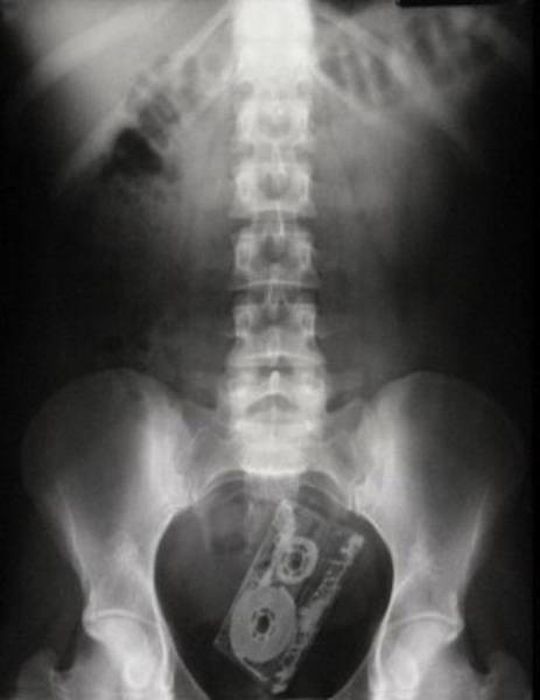

Предметы, которые не очень хочется видеть внутри себя

Под рентгеновскими лучами порой видны не только внутренние органы и кости, но и инородные тела, попавшие в организм

Истории попадания этих предметов в организм могут быть самыми невероятными и запутанными, но больше всего медиков интересует процесс их извлечения, впрочем, в этом заинтересованы и сами пациенты, допустившие нечто подобное со своим телом.